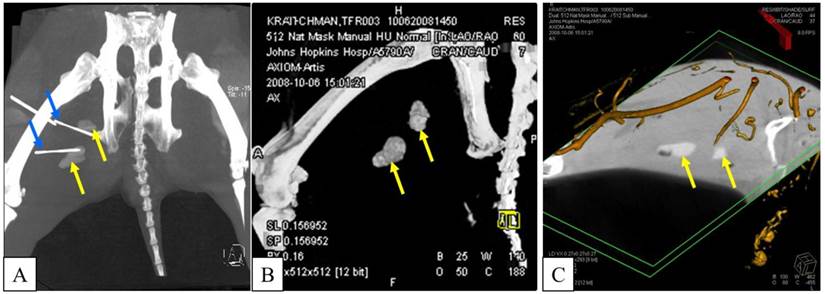

Figure 7

A, B: APA-TF-MSCs (left side of the image) are not visible on c-arm CT, while PFOB-TF-MSCs injections (yellow arrows, right thigh) are easily detectable. Blue arrows indicate needles guided to the PFOB-TF-MSCs transplant locations. C: In the same animal case, an embedded multiplanar reconstruction of c-arm CT with a digital subtraction angiogram indicates the localization of transplanted PFOB-TF-MSCs (yellow arrows) relative to vasculature (orange).